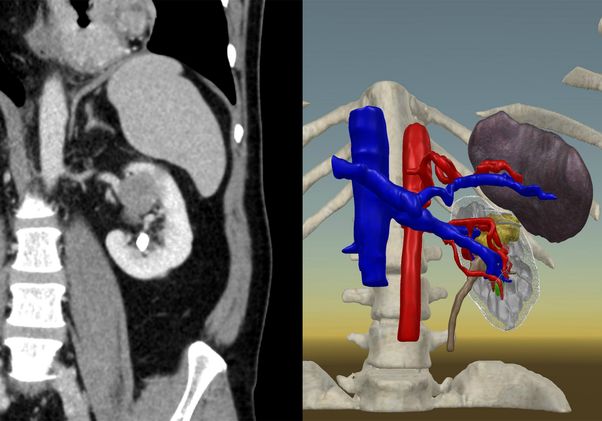

The 3D model provides surgeons with a better visualization of a person’s anatomy, allowing them to see the depth and contour of the structure, as opposed to viewing a two-dimensional picture.

For those in the control group, the surgeon prepared for surgery by reviewing the patient’s CT or MRI scan only. For those in the intervention group, the surgeon prepared for surgery by reviewing both the CT or MRI scan and the 3D virtual reality model. The 3D models were reviewed by the surgeons from their mobile phones and through a virtual reality headset.

“Visualizing the patient’s anatomy in a multicolor 3D format, and particularly in virtual reality, gives the surgeon a much better understanding of key structures and their relationships to each other,” Shirk said. “This study was for kidney cancer, but the benefits of using 3D models for surgical planning will translate to many other types of cancer operations, such as prostate, lung, liver and pancreas.”